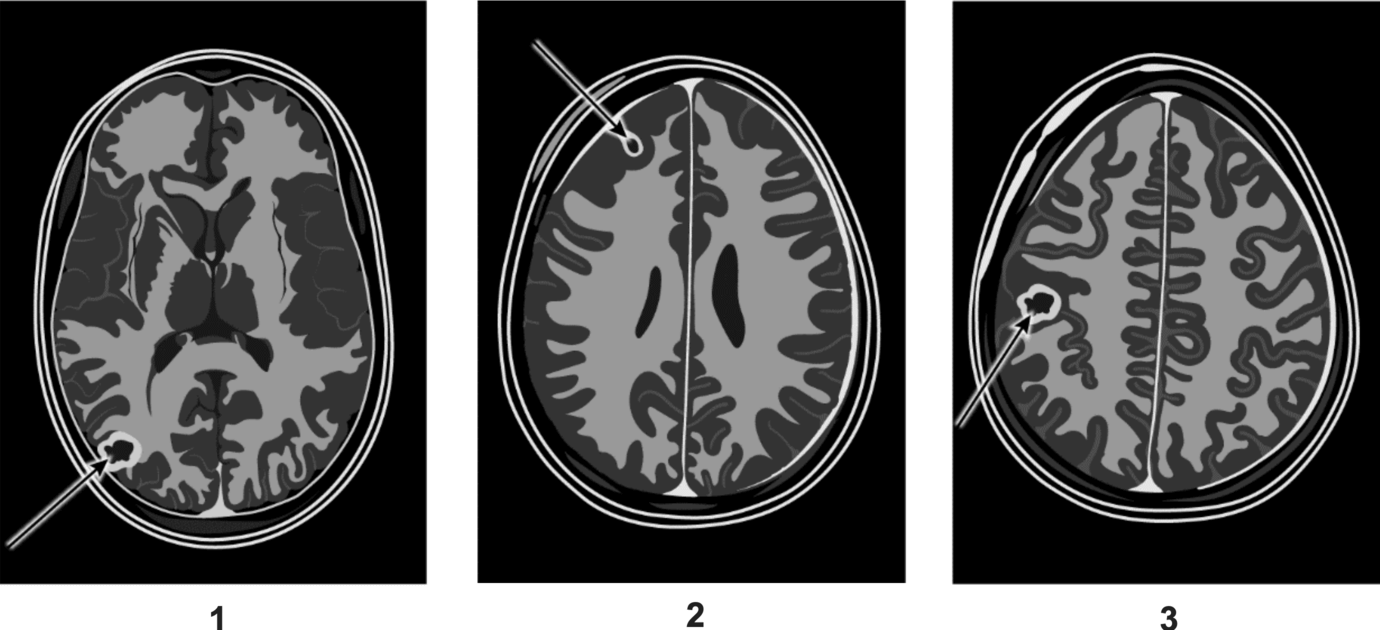

Op deze pagina behandelen we vraag 37 van het centraal examen biologie havo 2025 – tijdvak 1. Deze vraag is onderdeel van Gevaarlijke sporen, en is 1 punt waard.